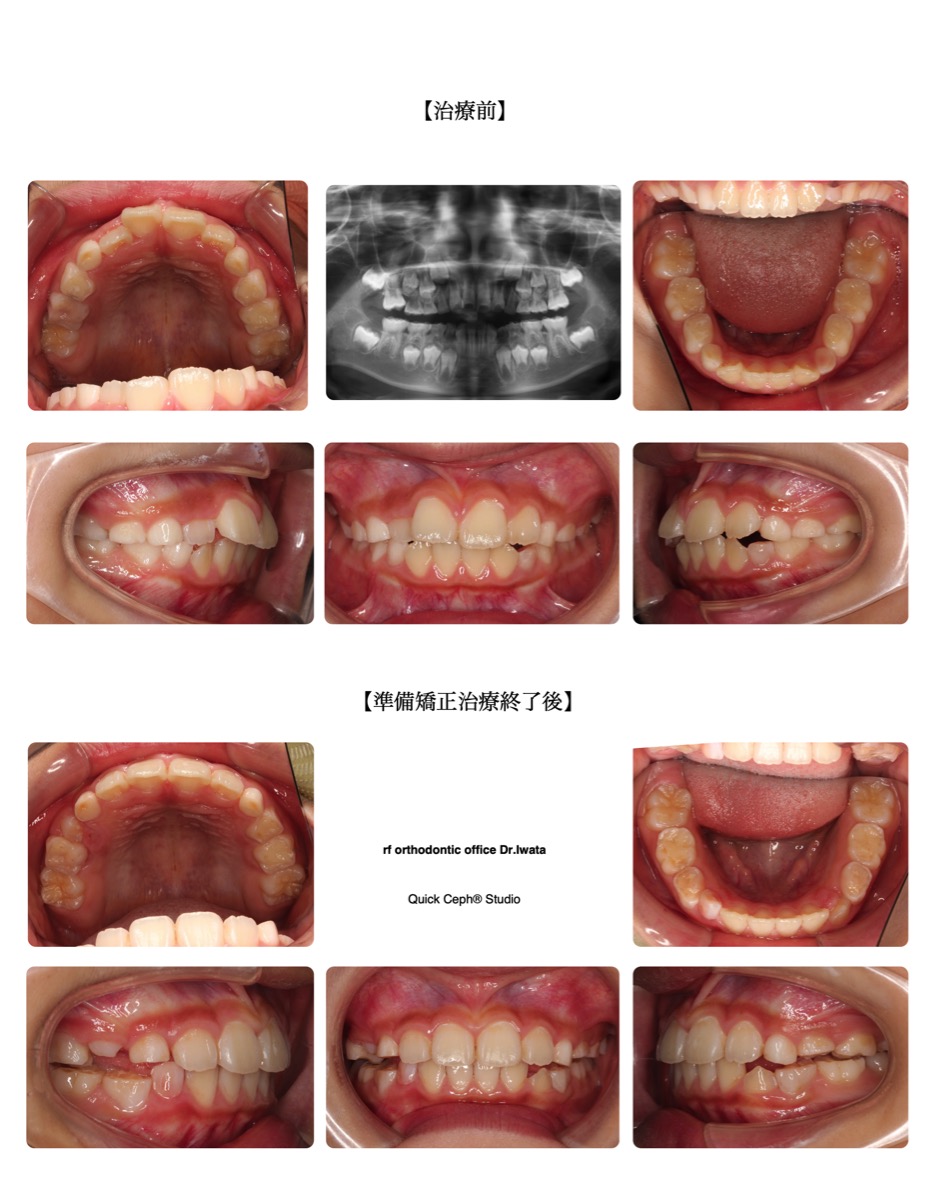

【主訴】上の出っ歯とすき間がどんどん目立ってきたので矯正を始めたい。口元も出ていて普段口が閉じづらい。できれ…